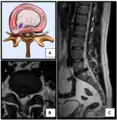

- Click images to see larger versions

Lumbar disc lesions, classification

Normal situation and spinal disc herniation in cervical vertebrae

Illustration depicting herniated disc and spinal nerve compression

Nucleus herniating through tear in annulus (with MRI)[7]

Illustration showing disc degeneration, prolapse, extrusion and sequestration.

- Magnetic resonance imaging (MRI) without contrast is a diagnostic test that produces three-dimensional images of body structures using powerful magnets and computer technology. It can show the spinal cord, nerve roots, and surrounding areas, as well as enlargement, degeneration, and tumors. It shows soft tissues better than CAT scans. An MRI performed with a high magnetic field strength usually provides the most conclusive evidence for diagnosis of a disc herniation. T2-weighted images allow for clear visualization of protruded disc material in the spinal canal.

MRI scan of cervical disc herniation between C5 and C6 vertebrae.

MRI scan of cervical disc herniation between C6 and C7 vertebrae

MRI scan of large herniation (on the right) of the disc between L4 and L5 vertebrae

A rather severe herniation of the L4–L5 disc

Example of a herniated disc at L5–S1 in the lumbar spine